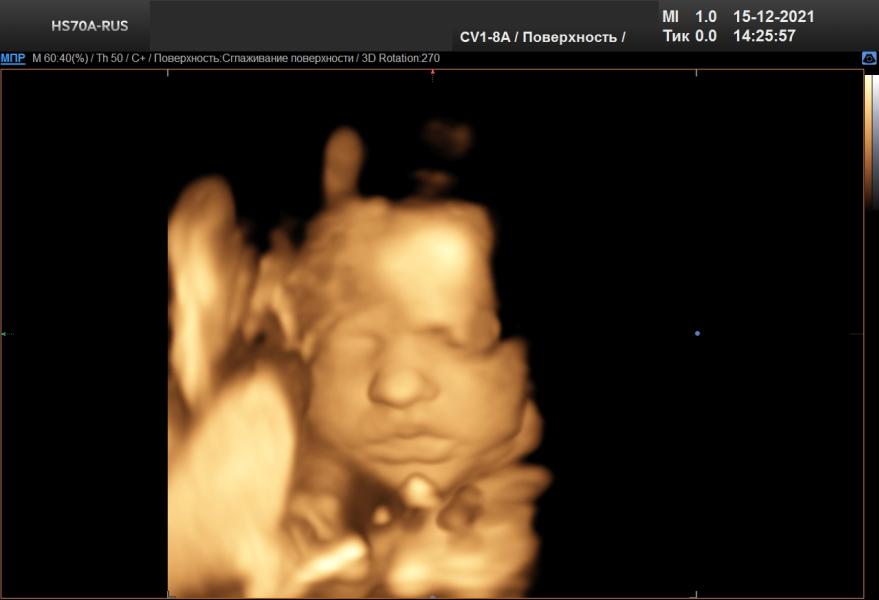

Третий скрининг) 3D) показывала нам язык, хлопала глазками и тянула кулачки в рот))

Наоборот, врач сказала, что на более поздних сроках, чем у меня, дети фиксируются и так сильно не шевелятся как было в моем случае и видно четче